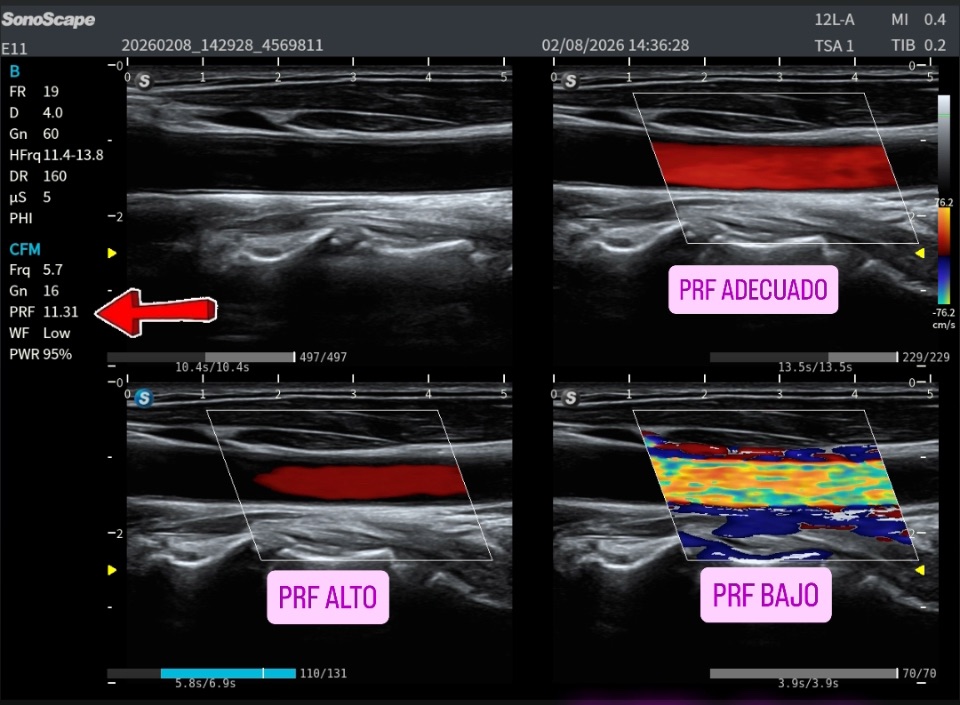

La Técnica Ecográfica:

Para identificar correctamente el Platisma, es imprescindible simplificar la técnica. Se requiere una sonda de alta frecuencia, cuanto más alta mejor, no se recomienda Sonda Stick Hockey porque es un músculo muy ancho y largo, de mucha variabilidad presencial anatómica, con el foco en el plano superficial y una profundidad ajustada. Si estos parámetros no son adecuados, el platisma no se visualizará, no porque no esté presente, sino porque la exploración no es correcta. Es muy importante un control especial de la TGC y los Armónicos y otros optimizadores de imagen activados siempre, ojo, porque algunos grados elevado de estos optimizadores pueden «pastelar» demasiado la imagen, necesitamos ver la ecotextura muscular, palabra nueva, que me encanta.